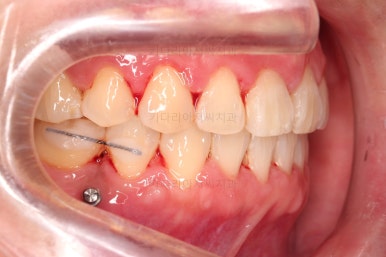

브라켓을 부착합니다.

이번 환자분이 선택하신 장치는 데이몬 클리어라고 하는 자가결찰 세라믹 장치인데요.

일반적으로 흔히 아시는 클리피씨 장치에 비해서 철사를 잡아주는 뚜껑까지 세라믹으로 되어 있어서 아마도 현존하는 세라믹 장치 중에서는 가장 심미적인 장치라고 볼 수 있습니다.

대신, 세라믹으로 되어 있다보니 강도 때문에 부피는 조금 더 커진다는 단점은 있긴 합니다.

중앙선 개선을 위해 미니스크류와 다양한 장치를 활용해 주고요.